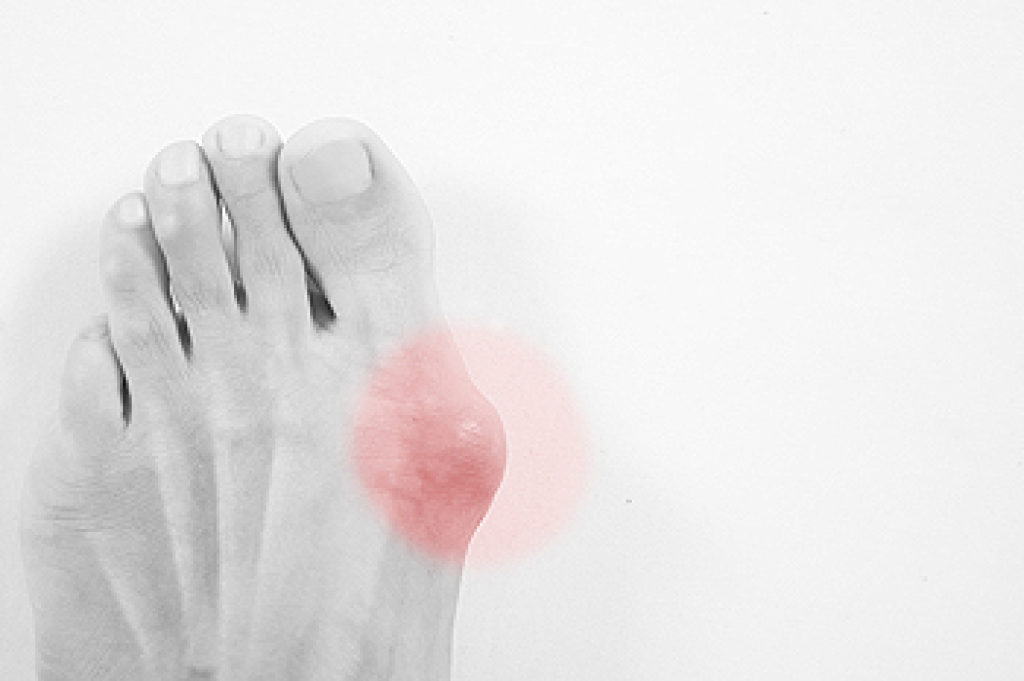

Heel spurs are bony growths that develop on the heel bone due to long-term strain on foot muscles and ligaments. They often form where the plantar fascia connects to the heel, causing discomfort and inflammation. Common causes include repetitive stress, wearing improper footwear, and prolonged standing. Risk factors such as flat feet, obesity, and age can increase the likelihood of developing them. There are two main types. Plantar heel spurs located under the heel and dorsal heel spurs form on the back near the Achilles tendon. Symptoms include sharp pain, tenderness, or stiffness. A podiatrist can diagnose heel spurs through an examination and imaging tests, and provide treatments that reduce pain and improve mobility. If you have heel pain, it is suggested that you schedule a visit with a podiatrist for an accurate diagnosis and treatment.

Heels Spurs

Heel spurs are formed by calcium deposits on the back of the foot where the heel is. This can also be caused by small fragments of bone breaking off one section of the foot, attaching onto the back of the foot. Heel spurs can also be bone growth on the back of the foot and may grow in the direction of the arch of the foot.

Older individuals usually suffer from heel spurs and pain sometimes intensifies with age. One of the main condition's spurs are related to is plantar fasciitis.

Pain

The pain associated with spurs is often because of weight placed on the feet. When someone is walking, their entire weight is concentrated on the feet. Bone spurs then have the tendency to affect other bones and tissues around the foot. As the pain continues, the feet will become tender and sensitive over time.